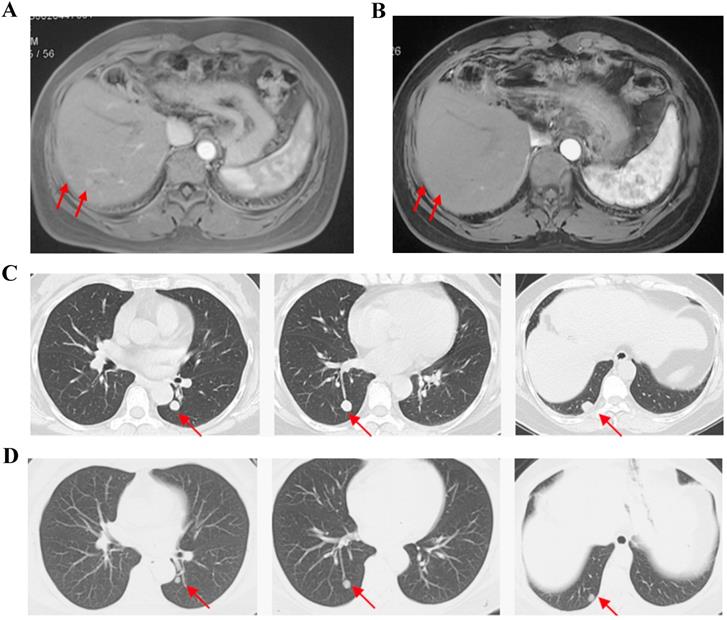

Cases Show partial response with apatinib monotherapy. Case 1, F/35y, relapsed with 2 foci in liver after surgery and TACE (a), achieved partial response after receiving apatinib 500 mg/d for 2 months and the response duration was 2 months (b). Case 2, F/54y, relapsed with 3 metastatic foci in lung after surgery, chemotherapy and TACE (c), achieved partial response after apatinib 500 mg/d for 3.5 months and the response duration was 2 months (d).

For FAS, the ORR was 11.5% and the DCR was 50.0% (Table 2). No patient achieved complete response (CR). 3 patients achieved partial response (PR) and the mean time of response duration was 2 months (Figure 1). 10 patients achieved stable disease (SD) and the mean time of response duration was 2.6 months, ranging from 1.5 months to 5 months. Kaplan-Meier curves estimated that the median PFS was 2.0 months (95% CI, 0.7-3.3) and the median OS was 9.0 months (95%CI, 4.6-13.4) (Figure 2).